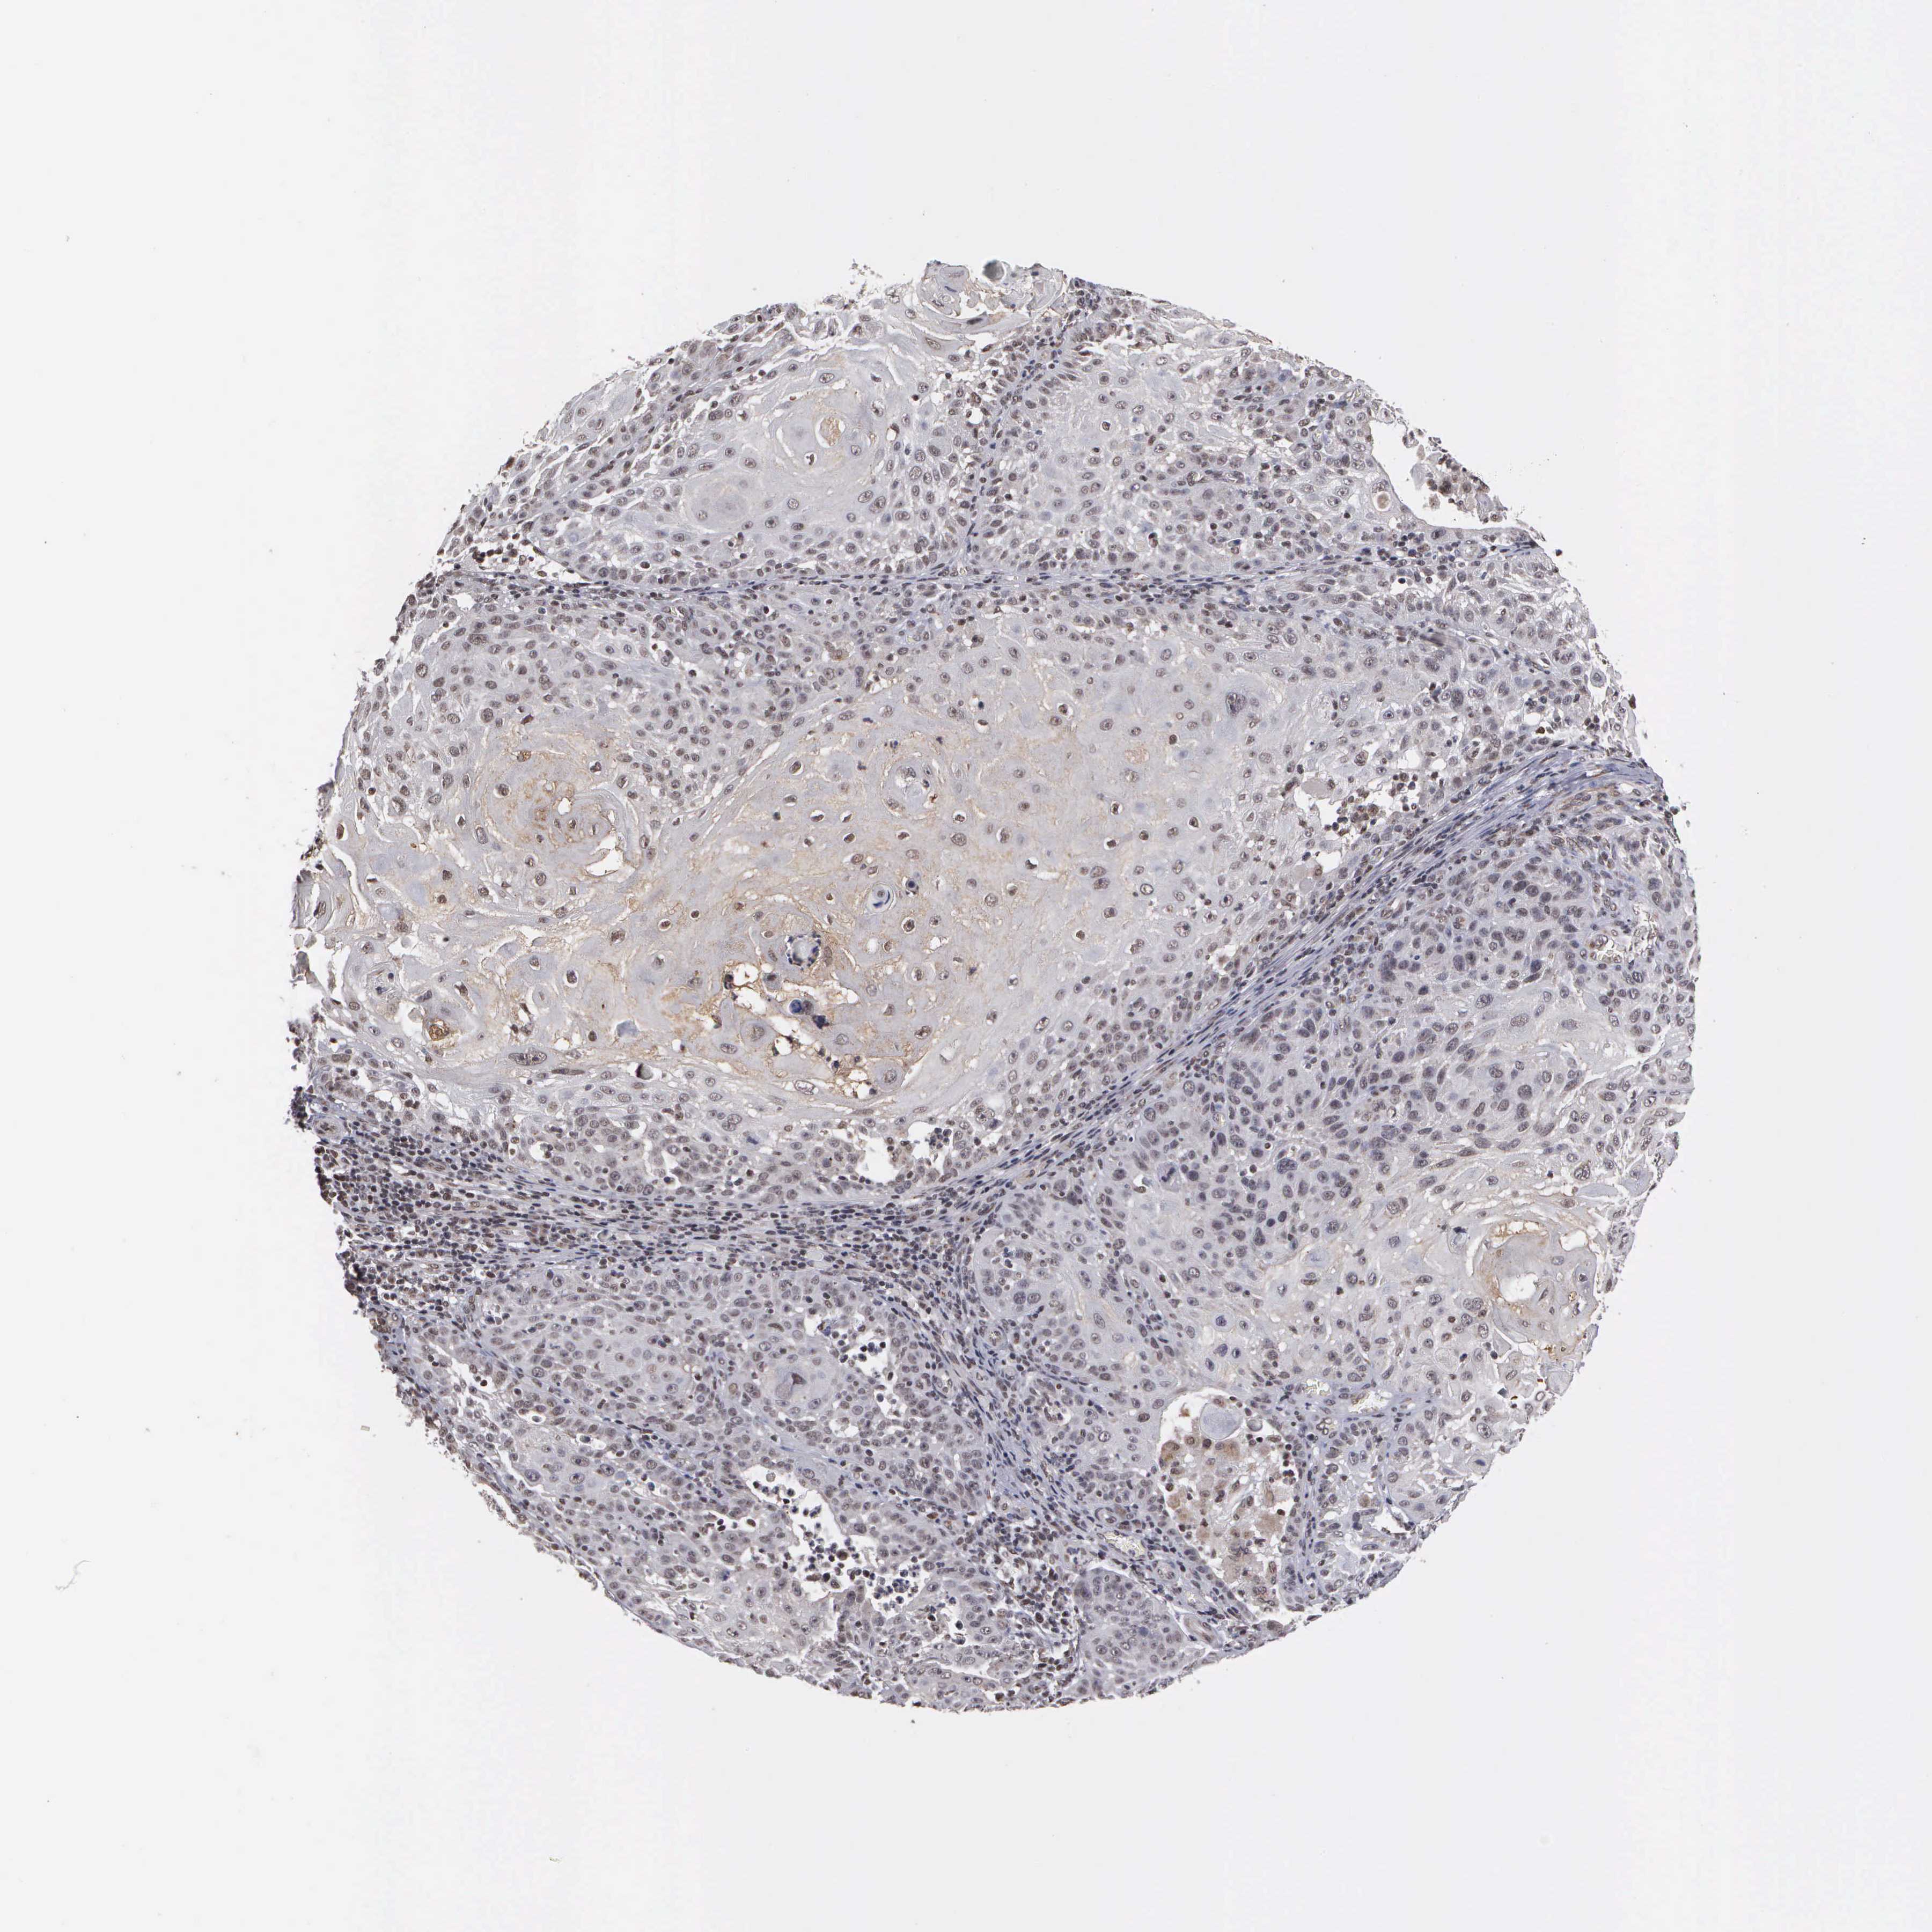

SKIN CANCER - Protein expressioni

A mouse-over function shows sample information and annotation data. Click on an image to view it in a full screen mode. Samples can be filtered based on level of antibody staining by selecting one or several of the following categories: high, medium, low and not detected. The assay and annotation is described here.

Antibody staining in the annotated cell types in the current human tissue is reported as not detected, low, medium, or high, based on conventional immunohistochemistry profiling in selected tissues. This score is based on the combination of the staining intensity and fraction of stained cells.

Each image is clickable and will lead to virtual microscopy that enables deeper exploration of all samples and also displays staining intensity scores, fraction scores and subcellular localization as well as patient and tissue information for each sample.

Antibody HPA000869

Squamous cell carcinoma, NOS